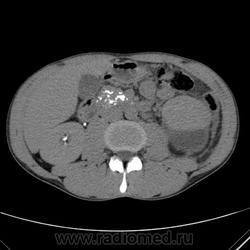

Паранефральная или субкапсулярная гематома?

Каменючки в поджелудочной железе?

Каменючка в левом мочеточнике?

Субкапсулярная, Валентин Львович. Только гигрома, на мой взгляд. И каменючки)). И еще кое-что.

Кпереди и латеральнее верхнего полюса левой почки-ограниченное жидкостное образование,не абсцесс-ли?

Вот и думаю)). Вроде и в области травмы, тут же. Вроде и связь с селезеночным углом толстой кишки есть... Не температурит (пока), кровь спокойная. но жидкость там по флангу маленько, да и в малом тазу тоже...

В мочеточниках - контраст, не камешки.

С другой стороны, у парня хронический панкреатит,может это псевдокиста,они ведь могут вылезать где угодно!

Думаю, что эта версия ближе к истине, потому что хр.калькулезный панкреатит+единичный кальцинат в стенке этого кистовидного образования. Вероятнее всего, как раз и есть постпанкреатическая киста с вялотекущим воспалительным процессом. Так и написала в заключении.

Был еще вариант микроперфорации толстой кишки, но что-то он мне душу не согрел)))

но скорее всего, вторичный, за счет оттеснения почки кпереди гигромой.